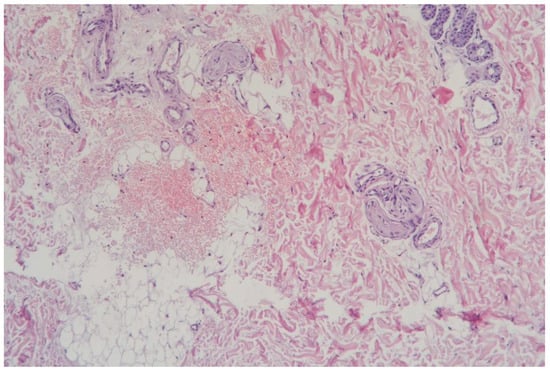

3.1.3. Clinical Case 3: Soft Tissues in the Dissection Area, Scar 20 W (See Figure 4)

Description: The histological examination showed preserved epidermis and underlying dermis. The vessels of the superficial vascular plexus were dilated, while those of the deep plexus collapsed. There was noted collagen fiber densification at the biopsy edge. No inflammatory changes were observed, and the skin appendages remained intact.

Figure 4.

Skin changes in Rat 1 on the 7th day after exposure to the thulium laser at 20 W, 100 Hz. H&E staining, 10× objective magnification.

On the 7th day after exposure to the thulium laser at 20 W, the tissues were almost completely restored, with scar tissue formation characterized by slightly densified collagen fibers.